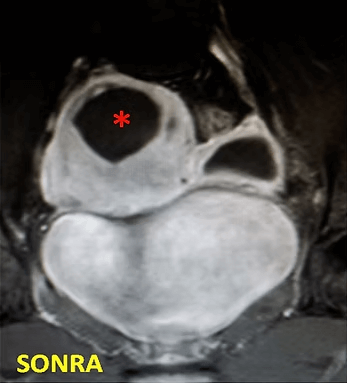

44 yaşında, kabızlık, gaz, sık idrara çıkma şikayetleri mevcut. Emar’da idrar kesesine bası yapan 3 miyom (*) izleniyor ve tek çare olarak histerektomi öneriliyor. Embolizasyondan sonra miyomların öldüğü ve küçüldüğü izleniyor. İşlemden 6 ay sonra hasta şikayetleri tama yakın azalmıştır.